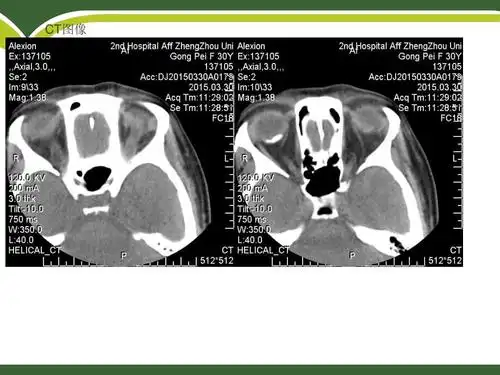

脉络膜骨瘤多种眼底影像特征对比观察

脉络膜骨瘤